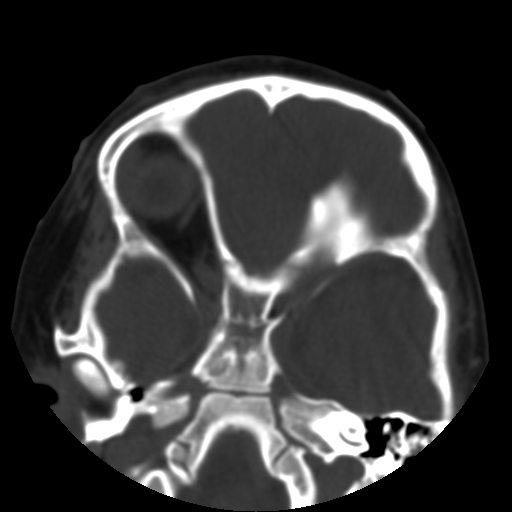

以下是引用深泽交通医院在2009-10-16 8:25:00的发言:[br]右眼环出血伴异物

以下是引用卜一在2009-10-16 15:01:00的发言:[br]右眼球挫裂伤伴异物!

以下是引用拾荒者在2009-10-17 18:38:00的发言:[br]鼻面部皮下积气,右侧睑缘及眼球壁高密度异物影,左侧眼球壁晶状体内侧缘处是圆形低密度影。低密度异物?应提请眼科医生注意。